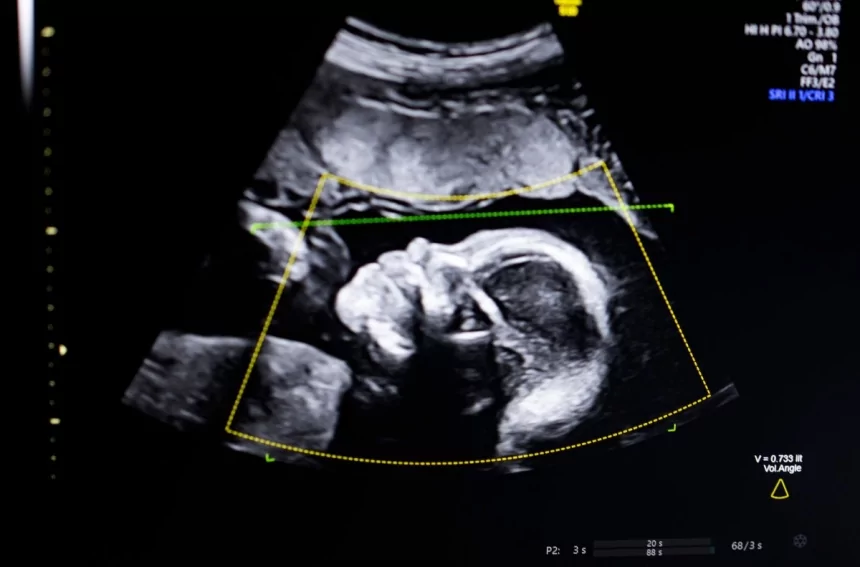

TechCrunch Disrupt Battlefield 2023 winner, BioticsAI, announced on Monday that it has received FDA clearance for its AI software that helps detect fetal abnormalities in ultrasound images.